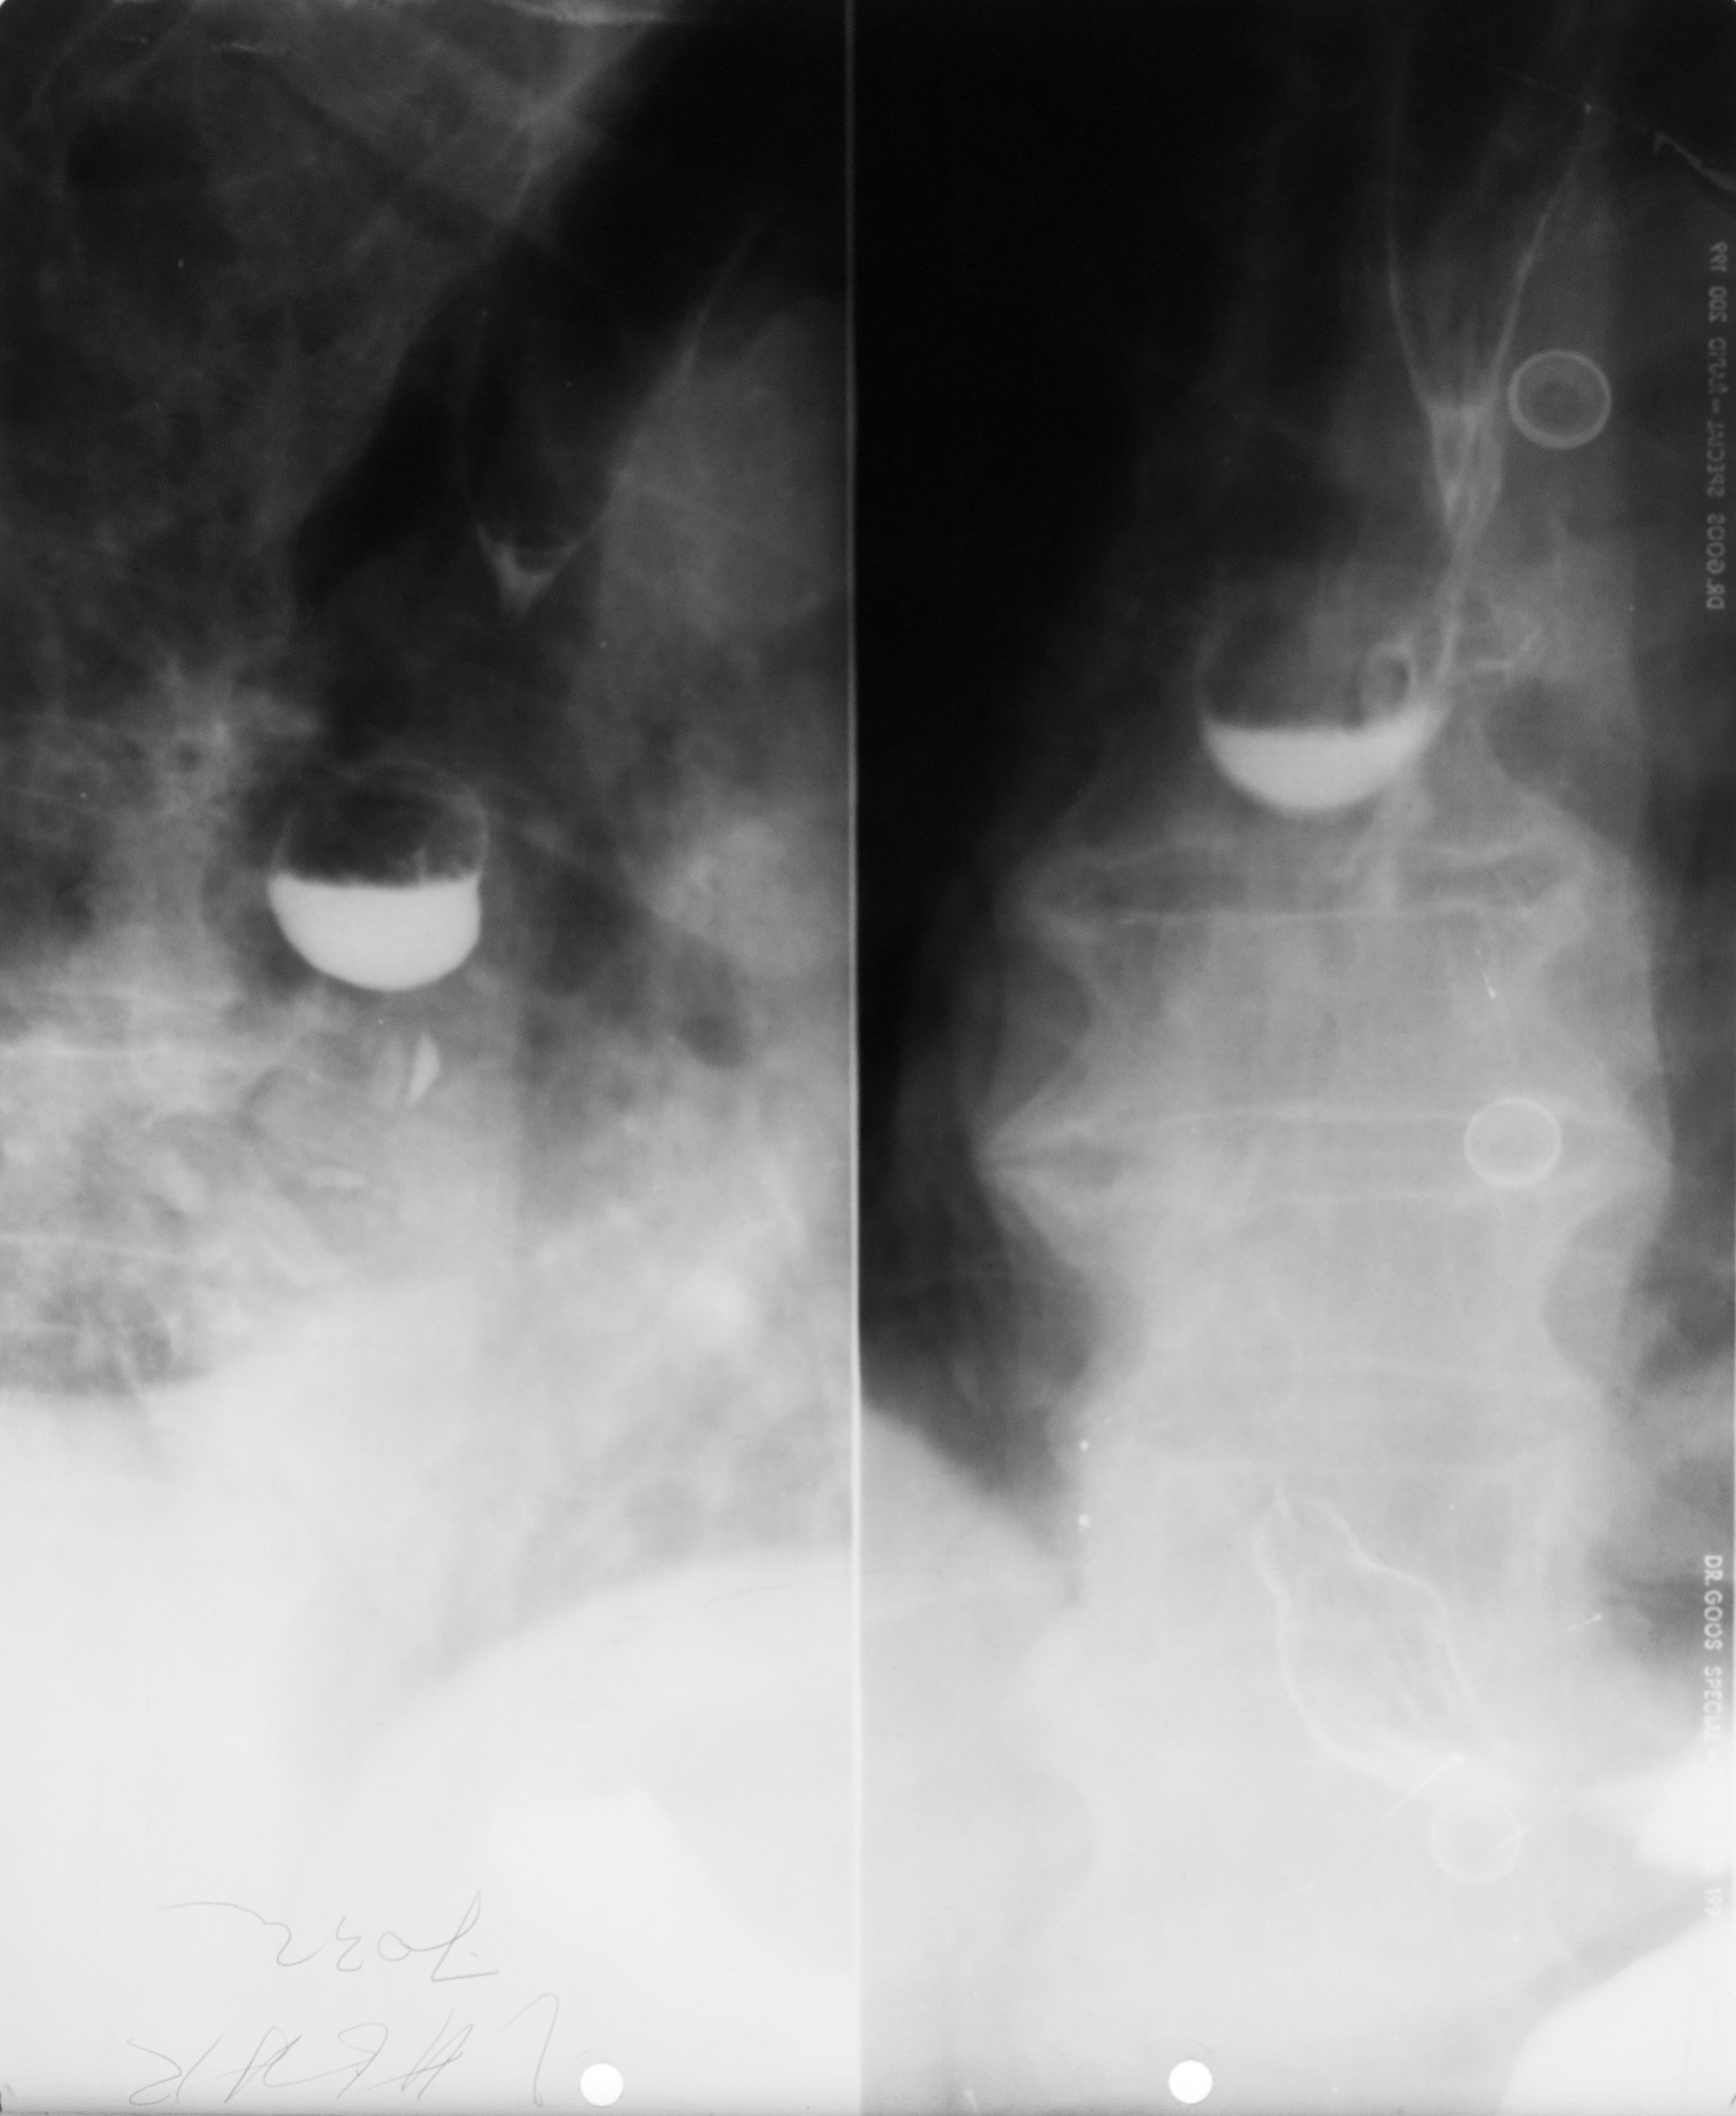

DIVERTICUL ESOFAGIAN

Tranzit baritat pe regiunea toracală

Se observă esofagul plus o imagine adiacentă a acestuia cu un camp de umplere,cu nivel orizontal și hipertransparență deasupra.

DIVERTICUL ESOFAGIAN

Tranzit baritat la nivelul esofagului.

Se observă o imagine de adiție(iese din conturul organului)

DIVERTICUL ZENKER

Tranzit baritat a esofagului pe radiografie de profil.

Se observă esofagul din profil,coloana vertebrală,imaginea de adiție cu substanță de contrast în interior și aer antidecliv

DIVERTICUL ZENKER( Văzut din față)

Pată persistentă de substanță de contrast,văzută din față,în proiecția mediastinului superior